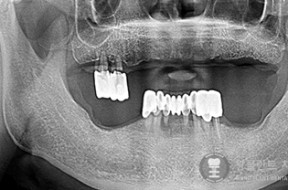

전후사례